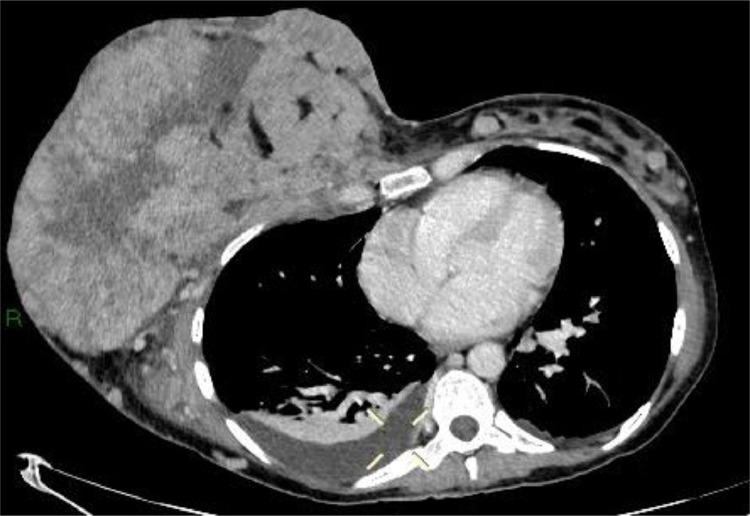

Pregnancy-associated breast cancer (PABC) presents unique challenges. This type of breast cancer is often more aggressive than that diagnosed in nonpregnant women, and its diagnosis is frequently delayed. Several factors contribute to this delay, including the physiological changes that occur during pregnancy, such as breast enlargement, breast tenderness and increased tissue density, which can mask early signs of malignancy. Additionally, a lack of awareness among healthcare providers can lead to symptoms being dismissed as normal pregnancy-related changes, and then being underestimated. Consequently, PABC is often diagnosed at more advanced stages, which can result in a poorer prognosis for the patient. This case study reports a 36-year-old woman in good general health, who received histological diagnosis of breast cancer during her pregnancy after presenting for self-detection of an enormous palpable breast mass. Prior to hospitalization, the patient had been treated with antibiotics in the mistaken belief that it was infectious mastitis; subsequently, considering the huge dimensions of the mass and the presence of lymph node metastases, neoadjuvant chemotherapy was started until induction of labor. Imaging techniques such as ultrasonography (and mammography as an adjunct) and nonenhanced MRI (due to potential toxicity of gadolinium to the fetus) can be used for staging maternal breast disease during pregnancy. A multidisciplinary approach which involves the radiologist, the breast surgeon, the oncologist and the gynecologist is fundamental to ensure the best prognostic outcomes for both the mother and the fetus.

妊娠相关乳腺癌(PABC)带来了独特的挑战。这种类型的乳腺癌往往比非妊娠女性所诊断出的乳腺癌更具侵袭性,而且其诊断常常被延迟。有几个因素导致了这种延迟,包括怀孕期间发生的生理变化,如乳房增大、乳房压痛和组织密度增加,这些变化可能掩盖恶性肿瘤的早期迹象。此外,医疗保健提供者缺乏认识可能导致症状被视为正常的妊娠相关变化而被忽视,进而被低估。因此,PABC往往在更晚期才被诊断出来,这可能导致患者预后较差。本病例报告了一名36岁总体健康状况良好的女性,她在怀孕期间自行发现一个可触及的巨大乳房肿块后接受了乳腺癌的组织学诊断。在住院之前,患者因误以为是感染性乳腺炎而接受了抗生素治疗;随后,考虑到肿块巨大且存在淋巴结转移,开始进行新辅助化疗直至引产。超声检查(以及作为辅助手段的乳腺X线摄影)和非增强MRI(由于钆对胎儿可能存在毒性)等成像技术可用于在怀孕期间对母体乳腺疾病进行分期。涉及放射科医生、乳腺外科医生、肿瘤内科医生和妇科医生的多学科方法对于确保母亲和胎儿获得最佳预后结果至关重要。